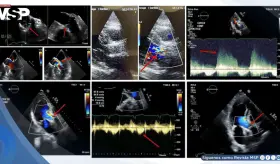

El cuadro se caracterizó por neumonía necrotizante, aleteo auricular con respuesta ventricular rápida, insuficiencia cardíaca biventricular y formación de trombos intracardíacos bilaterales.

Paciente con marcapasos reciente desarrolló endocarditis infecciosa por Staphylococcus epidermidis complicada con pseudoaneurisma del intervalo mitral-aórtico y perforación valvular mitral.